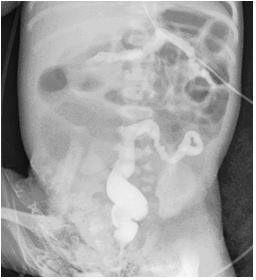

A contrast enema study was done on day 2 using non-ionicwater-solublecontrast to rule out large bowel obstruction and impacted meconium. Contrast study revealed a small calibered featureless colon i.e. microcolon with no filling defects within suggestive of distal small bowel obstruction.(Figure 4)

Figure 4: Contrast enema shows unused microcolon with no filling defects.

In addition, dilated gas filled bowel loops were in the background, suggestive of ileal atresia.